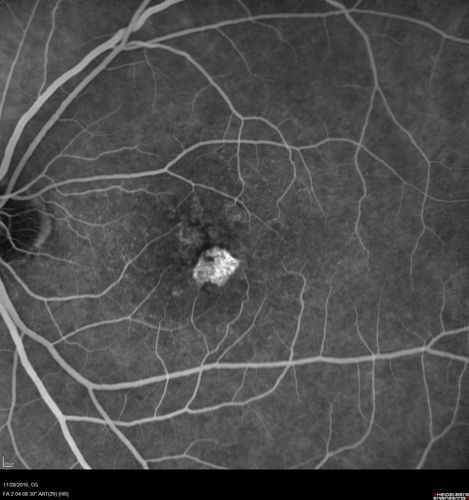

Confluent Soft Drusen with Subetinal Fluid - Right Eye

Asymptomatic 85 year old man.  OCT shows pocket of subfoveal fluid in the center of the macula.  This could be mechanical from the drusen preventing the retina from settling down.  Testing did not reveal a CNVM and subsequent OCT 6 weeks later showed no change in structure.